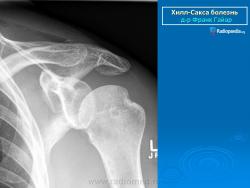

На рентгенограмме плечевого сустава определяется умеренный остеопороз головки плечевой кости. Иногда на ее задненаружной поверхности позади вершины большого бугорка выявляется вдавленный дефект (повреждение Хилл-Сакса). Дефект четко виден на рентгенограмме в аксиальной проекции. Аналогичный, но менее выраженный дефект может быть выявлен в зоне передненаружного края суставной впадины лопатки. Также в диагностике причин привычного вывиха плеча помогает МРТ исследование.

рентгенограмма плечевого сустава. Повреждение Хилл-Сакса и сопутствующий кальциноз сухожилий вращательной манжеты